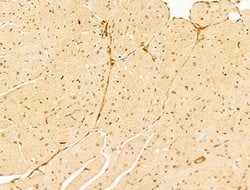

Invitrogen™ GABPB1 Polyclonal Antibody

Antibody detects endogenous levels of total GABPB1.

| Immunohistochemistry (Paraffin), Western Blot, Immunocytochemistry | |

| A synthesized peptide derived from human GABPB1(Accession Q06547), corresponding to amino acid residues V264-D314. | |

| Human, Mouse, Rat | |